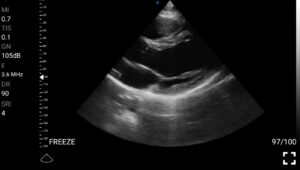

• Καρδιολογική Απεικόνιση για Κλινική Αξιολόγηση

• Διάγνωση περικαρδιακής συλλογής: Εκτίμηση πιθανής καρδιακής επιπωματισμού.

• Ανίχνευση περικαρδιακής συλλογής και καρδιακού επιπωματισμού.

Παραδείγματα

Ολες οι παραπάνω απεικονιστικές εξετάσεις έχουν ληφθεί από φορητή συσκευή όπως: Apple Iphone, Tablet, Samsung Mobile Phones και διάφορες άλλες φορητές συσκευές.

Παραδείγματα Video